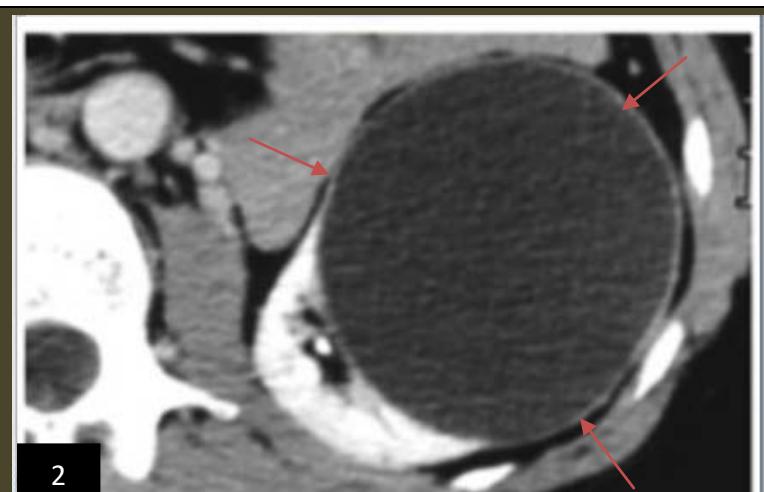

Iconography C: lower left renal polar cystic lesion, alcoholic. Image 1. showing an echo-empty (cystic) left lower renal polar mass,2. CT image showing a left lower polar hypodense mass 3. Ultra sonographic image in B mode showing subcutaneous anesthetic infiltration,4. Image of the left kidney in mode 12 months after sclerotherapy, 5. Image of a clear liquid that had been removed during sclerotherapy.